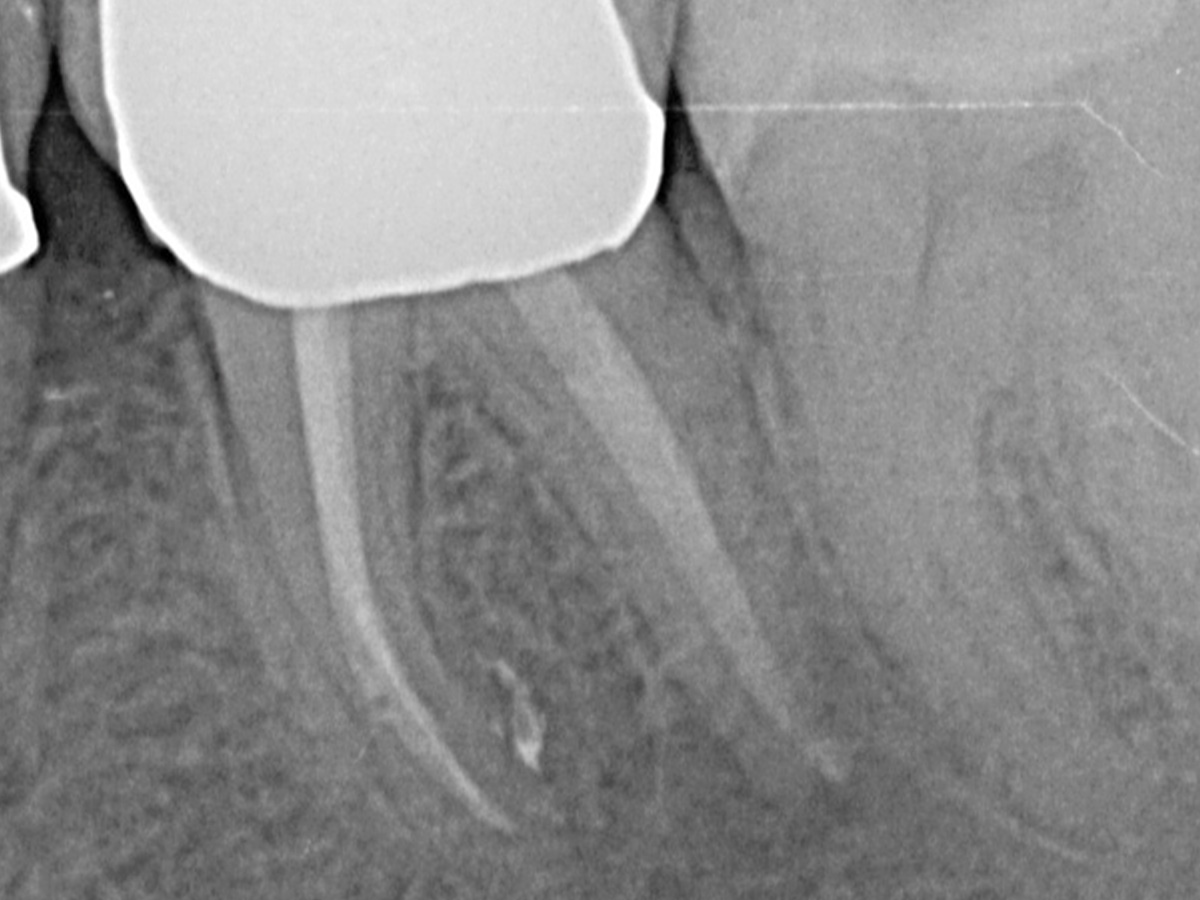

Sie erlernen die grundlegenden Bausteine eines evidenzbasierten endodontischen Behandlungskonzepts, welches langfristigenBehandlungserfolg garantiert.

• Moderne endodontische Diagnostik

• Biologische und mechanische Voraussetzungen für eine erfolgreiche Aufbereitung von Wurzelkanalsystemen

• 3D-basierte Planung der idealen endodontischen Zugangskavität und adäquaten minimalinvasiven Aufbereitung

• Techniken zur Bestimmung der idealen Arbeitslänge und Aufbereitungsgröße